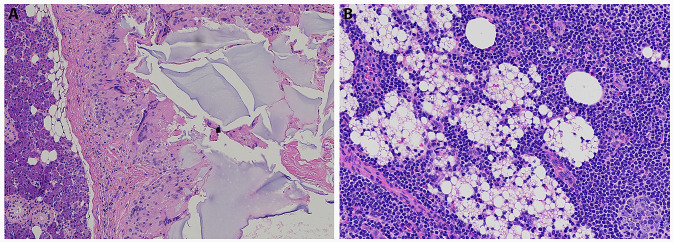

Pathology images demonstrated two distinct patterns of foreign bodies, suggesting this patient may have in fact received various forms of soft tissue filler injections, or a combination of substances. The images of the periparotid soft tissue (Fig. 2a) contained amorphous, slightly basophilic foreign bodies on H&E staining, suggestive of hyaluronic acid or polyacrylamide gel [8].

Fig. 2.

a Histological image (H&E stain) of the parotid mass demonstrating evidence of foreign body reaction. b Histological image (H&E) of intraparotid lymph node demonstrating foreign body substance and reaction

In the pathology image of the involved intraparotid lymph node (Fig. 2b), there are many small, round, nonstaining spaces in the tissue, suggestive of silicone, which is another permanent injectable and one that is more likely to present with delayed adverse reactions [8]. However, the original filler material could not be identified on histological review.